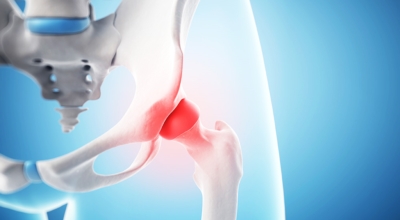

고관절이란 골반을 지탱하는 관절로서 근육과 힘줄로 구성되어 있어요. 학계에서는 고관절을 엉덩이 관절이라고 부르기도 하며 인체의 하중을 지탱하는 아주 중요한 관절입니다. 각별히 고관절은 우리가 정상적으로 서있거나 움직일 수 있게 만들어주며 달리기, 점프, 무거운 무게를 들 때 최대 체중의 2~10배 가량의 하중을 받기 때문에 적절한 관리가 필요합니다. 오늘은 고관절에서 일어날 수 있는 고관절 통증 증상에 관해서 알려드리도록 하겠습니다.

고관절염은 고관절에 나타나는 관절염을 말하며 고관절의 연골이 닳게 되면서 뼈와 뼈가 서로 부딪히며 통증을 일으키게 돼요. 고관절염 초기 증상으로는 사타구니 부위가 불편하게 느껴지며, 무리하면 통증이 발생할 수 있으며, 관절염 증상이 심해지면서 사타구니에서 느끼던 통증이 허벅지와 엉덩이 통증으로 이어지기도 하는데, 고관절염 통증 증상으로 초기에는 허리 통증이 나타나 허리 질환과 혼동하기 쉬우며 각별히 척추질환이 있는 사람은 고관절 통증과 마찬가지로 엉덩이, 다리 통증이 동반되기 때문에 훨씬 헷갈리는 경우가 많습니다.